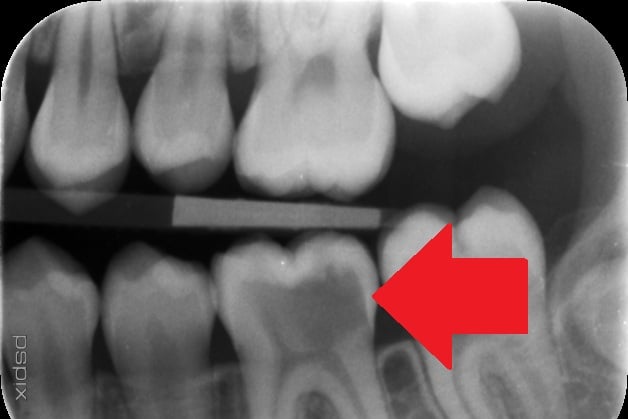

She was later seen by a different dentist, who carried out an X-ray. “That was the first time anyone really listened,” she said. “They told me one tooth was badly decayed and it had spread to two others.” The affected tooth was extracted when she was 15.

An investigation found the decay should have been diagnosed earlier.